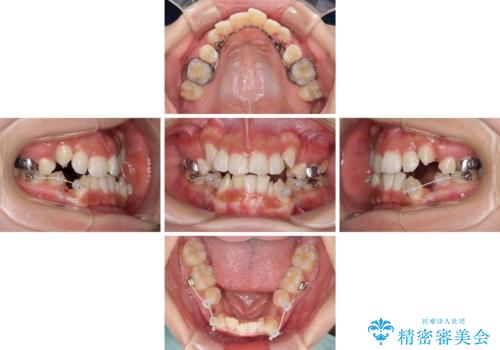

- 顕著な八重歯が気になるとのことで来院された患者様です。

インビザラインでの治療を希望されましたが、インビザライン単独では困難と判断されたため、補助装置や一部ワイヤー装置を用いて行うこととしました。

叢生が強いため、上下左右第一小臼歯4本を抜歯することとしました。

ワイヤー装置を用いた場合、一般的には2年程度で終了することを考えると、「移動量が多くなると治療期間が長くなる」というインビザライン矯正の最大の弱点が現れた治療となりました。